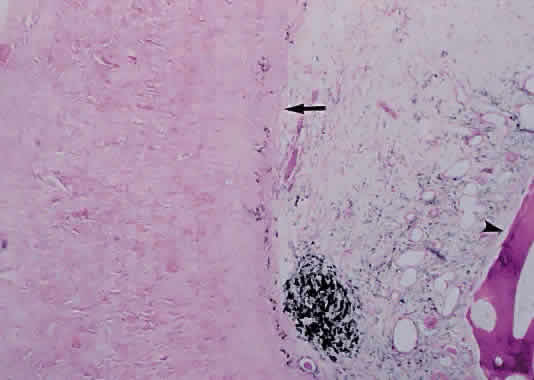

Acute nongranulomatous uveitis typically does not result in the need for enucleation or even biopsy; therefore, histopathologic examination of human eyes in the acute stages of the disease is rare. When enucleation is needed, it usually is at the end stage of the disease, when all attempts to preserve vision or comfort or both have failed. Thus, most histopathologic descriptions of human uveitis are from chronically inflamed eyes and show mostly an infiltration with chronic inflammatory cells (Fig. 2). Most of the information regarding events in acute uveitis has been gained from the use of various animal models of uveitis. Several models exist, but all are based on a similar principle: that of bypassing the normally existing state of self-tolerance and stimulating an organism to attack its own ocular tissues. This is accomplished by the subcutaneous inoculation of various substances (including retinal S antigen, interphotoreceptor retinoid-binding protein [IRBP], and melanin-associated proteins) into laboratory animals. A variable period later, depending on the specific model, uveitis develops, which can then be studied. In experimental autoimmune anterior uveitis, inoculation of Lewis rats with melanin-associated proteins produces primarily anterior segment disease,17–20 with minimal retinal involvement. Perhaps the most widely studied animal model of endogenous posterior uveitis is experimental autoimmune uveoretinitis (EAU), induced by the inoculation of either the retinal S antigen or IRBP into susceptible strains of animals. Other models of uveitis include bacterial product-induced intraocular inflammation. In endotoxin-induced uveitis, injection of bacterial endotoxins directly into the vitreous cavity or systemically produces inflammation localized primarily to the anterior segment in Lewis rats.21

Early events in EAU include expression of adhesion molecules on the surface of retinal vascular endothelium, allowing the adherence of circulating leukocytes and subsequent infiltration into the retina.22,23 In Lewis rats, the acute cellular infiltrate is composed of neutrophils and primarily affects the retina (Fig. 3) and anterior segment.24 CD4+ T cells have been found necessary for the development of EAU25 and are stimulated by presentation of antigen in the setting of MHC class II-expressing cells.26 There is likely a genetic susceptibility to the development of EAU,27 which may help explain occurrence of uveitis in only certain individuals. Once initiated, much of the damage resulting from EAU, and most likely in human uveitis, is caused by the production of numerous oxygen-derived radicals (e.g., superoxide, hydrogen peroxide, hydroxyl radicals, peroxynitrite), which directly attack the photoreceptor layer, producing oxidative damage to these sensitive light-sensing cells.28–30

Fig. 3. Photomicrograph of retina of Lewis rat 13 days after injection of S antigen in complete Freund's adjuvant to hind footpad. Inflammatory cell infiltrate exists within the retina as well as in the subretinal space. Photoreceptor layer is destroyed (hematoxylin and eosin; × 200).